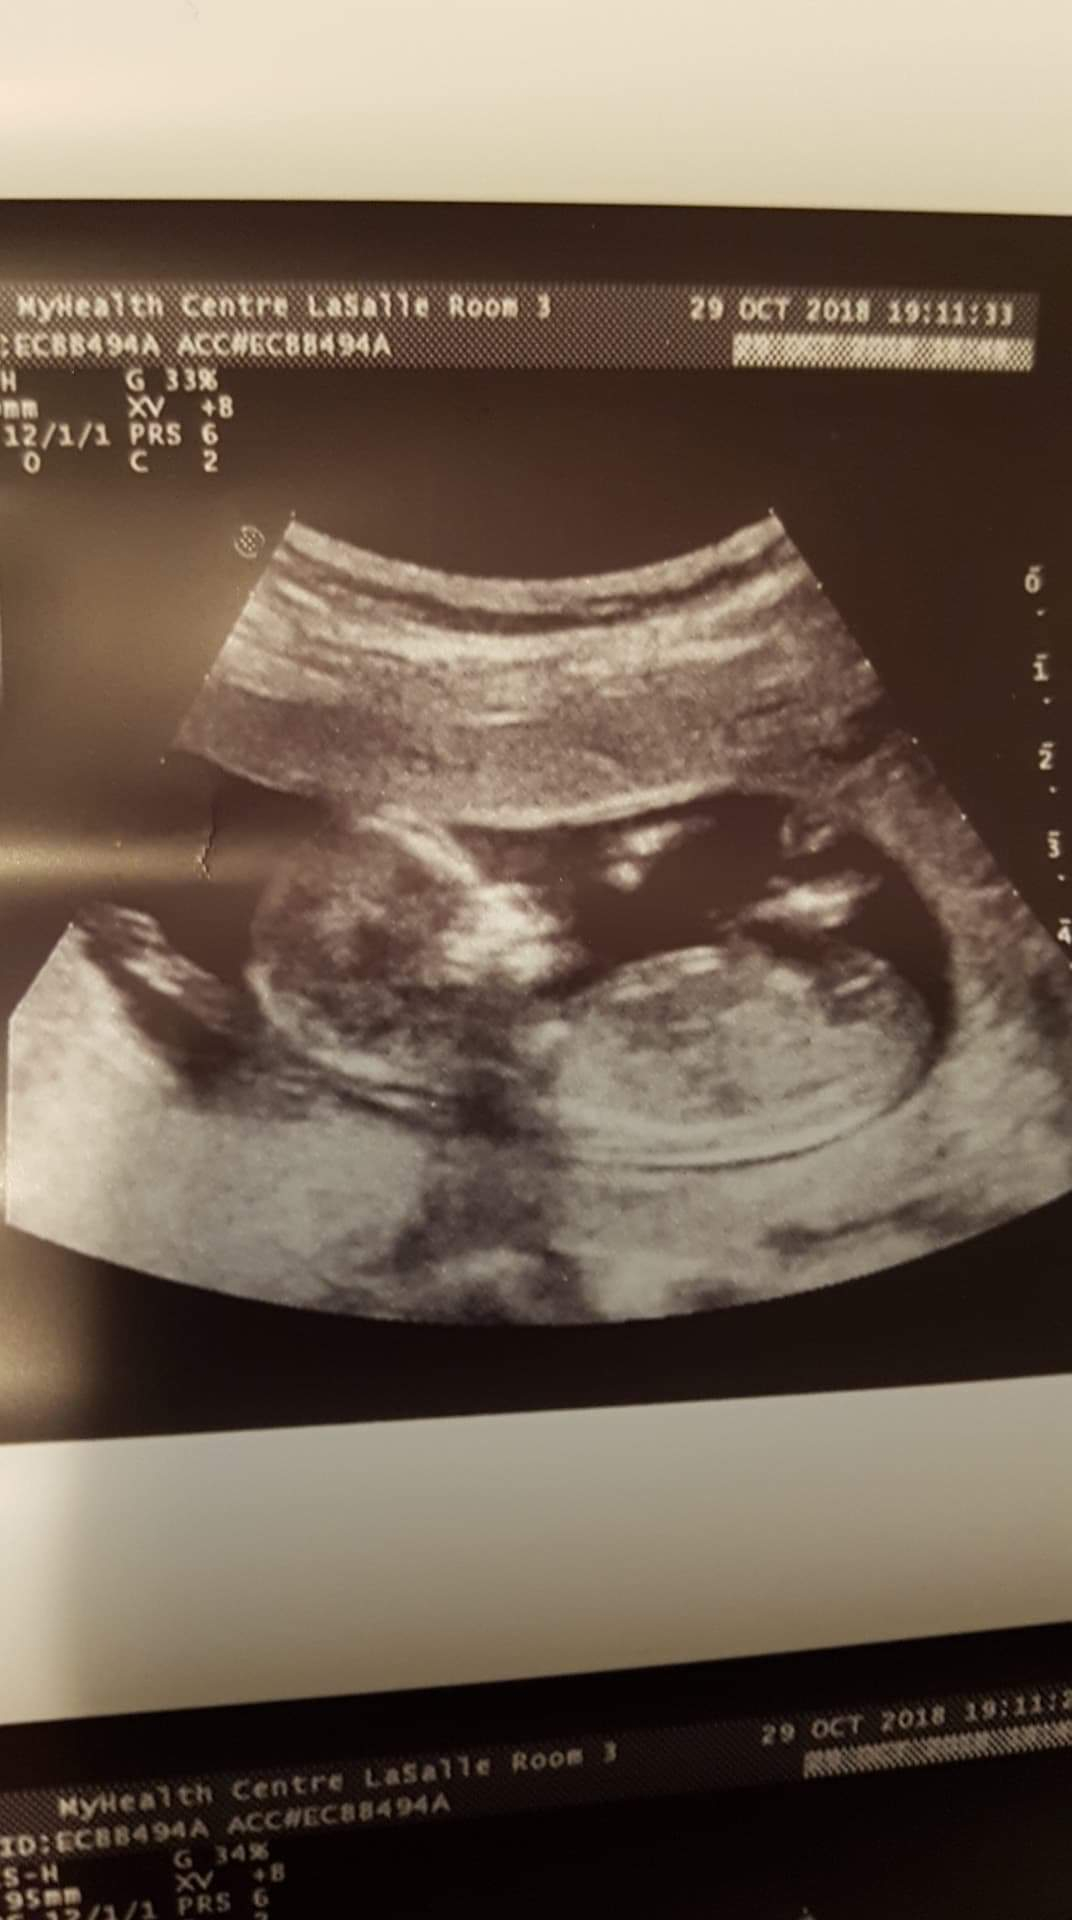

May 2019 Moms